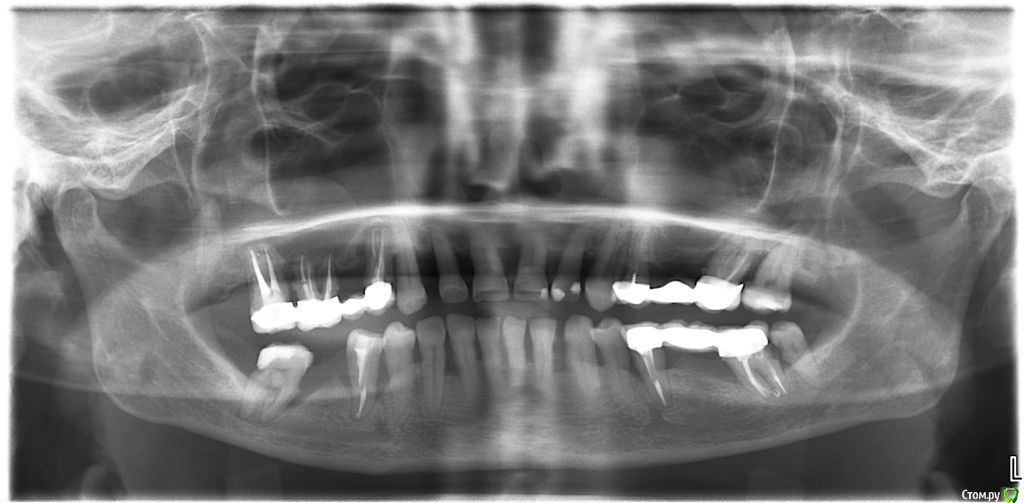

елена сок Опубликовано 11 февраля, 2019 Поделиться Опубликовано 11 февраля, 2019 Прошла 4 врачей - и все советуют РАЗНЫЙ комплекс лечения - от просто тщательной и постоянной гигиены до удаления зубов и имплантации. Мозг взрывается! Нужно определятся - а я не знаю, каким путем идти... Все же НЕ хотелось бы лишаться СВОИХ зубов.(если только, конечно, нет других вариантов...) Есть надежда, что получу понятную консультацию на этом форуме и смогу принять ПРАВИЛЬНОЕ решение. Заранее - всем СПАСИБО!!!!! Ссылка на комментарий

DmitrySH Опубликовано 11 февраля, 2019 Поделиться Опубликовано 11 февраля, 2019 и все советуют РАЗНЫЙ комплекс лечения - от просто тщательной и постоянной гигиены до удаления зубов и имплантации. Сложная ситуация, и без очного осмотра сложно что-то конкретное сказать. Но те кто смотрел, все правильно сказали. Минимально - это поддержание проф. гигиены. очень тщательно, после каждого приема пищи. обязательно с ирригатором. Максимально - удаление и имплантация. Ссылка на комментарий